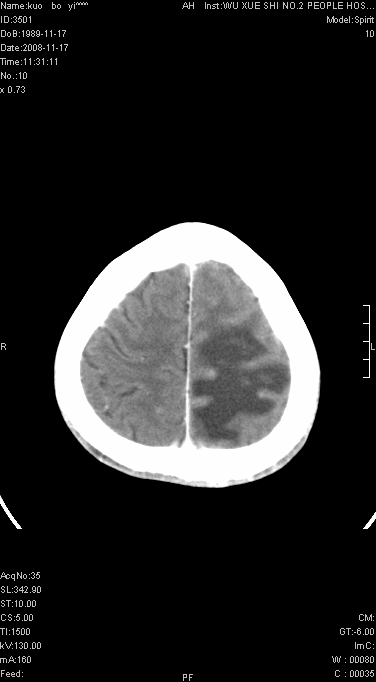

增强已传.年龄19岁.请会诊

增强后水肿中心高密度灶有明显强化,强化不均匀,呈雪花状或絮状,且强化明显,若为肿瘤,应该出现形态较规则的瘤体影,强也有例外如胶质瘤就可以形态不规则.但胶质瘤明显强化者多为恶性间变性,与病史及相关表现太不相符.因此本例多考虑为炎症引起.

左顶叶较大范围水肿区,内见明显强化的片状 棉絮状组织,但占位效应不明显。多考虑:脑炎!

左顶叶大范围水肿,内见明显强化的片状 棉絮状组织,但占位效应不明显。考虑脑炎可能性大。

在北京天坛医院治疗考虑寄生虫感.明显好转